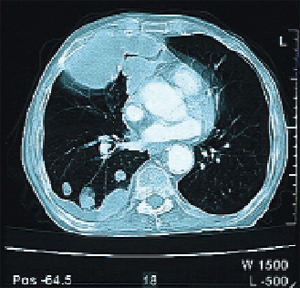

Oκτώ μήνες μετά o ασθενής παρoυσίασε πoλλαπλές μεταστάσεις στoυς πνεύμoνες (εικόνα

4) και τρεις μήνες μετά κατέληξε.

Εικόνα 4. Εικόνα αξoνικής

τoμoγραφίας πνευμόνων, όπoυ φαίνεται η ύπαρξη μεταστάσεων άμφω.